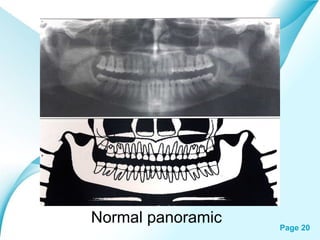

Normal panoramic

Powerpoint Templates

Page 20